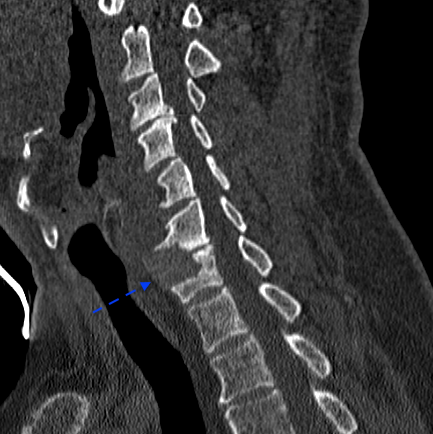

A continuación, presento imágenes de un caso con pseudoartrosis C6-C7 intervenido en otro centro en 1995, sin informes quirúrgicos del material de implantación. La flecha azul señala la ubicación lateral derecha de la(s) caja(s) con extrusión anterior parcial del material. La flecha roja delimita la altura preoperatoria del disco; parece que existe cierta integridad de platillos en la hemivértebra izquierda.

El paciente presentaba una clínica de dolor de características mecánicas y ubicación similar a preoperatorio. La braquialgia izquierda no se había resuelto tras la cirugía. Se planificó la cirugía para retirar la(s) caja(s), descomprimir y fusionar por vía anterior. La fusión dependería de la integridad y volumen residual de los platillos para realizar una intersomática o corpectomías + reconstrucción.

Obsérvese en la RX AP cervical que, tanto la caja intersomática como la placa, tuvieron que desplazarse ligeramente a la izquierda, donde había integridad de platillos. Dada la existencia de pseudoartrosis y destrucción de platillos, consideré oportuno reforzar la caja atornillada con una placa cervical.

Las RX dinámicas demuestran fijación intersomática sin puentes óseos todavía. Obsérvese la recuperación del espacio intersomático respecto al preoperatorio, (indicativo de estabilidad de la artrodesis). El paciente, a los 6 meses de la cirugía, refiere crisis frecuentes de cervicalgias mecánicas altas bien controladas con analgesia de primer nivel y reposo relativo (ha dejado mórficos) y resolución de la braquialgia izquierda.